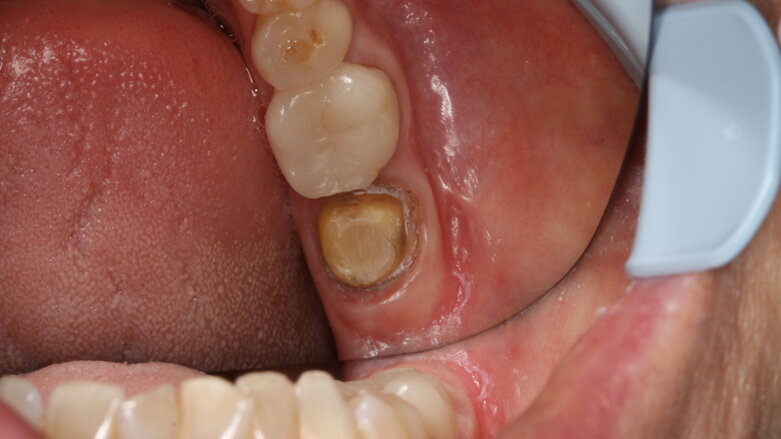

Initial situation of tooth #37. (Image: Dr Bernhild-Elke Stamnitz, Germany)

A case history demonstrates how CEREC Primescan proves its worth in everyday practice. A patient came to the practice with an inadequate crown, with secondary caries, in position #37. After excavation, a new CEREC crown was to be mounted. In order to do so, the new acquisition centre, CEREC Primescan AC, with its significantly larger, tiltable touch screen, was first disinfected. Thanks to the seamless surfaces, it is possible to do so quickly, thoroughly and simply, at any time. Before beginning with the scans, the patient data was retrieved in CEREC Primescan AC, and a new case was created. Overall, the scanner was used three times during treatment: after preparation of the lower dental arch with tooth #37, for the scan of the opposing dental arch and for the scan of the buccal bite on both sides.

After the scan, the software automatically delineates the preparation margin. If so desired, the margin can be adjusted manually. “I find that to be a great advantage,” says the digital expert, “because that way I can decide for myself every time whether I want to accept the suggestion—which, by the way, I generally do with a clear conscience.” It is operated via the touch screen (which replaces the trackball), a tool that many users, including Dr Stamnitz, wished for. Finally, the CEREC Software 5 made an initial suggestion. “I also always look at this very carefully,” she says. “The software can do a lot. I am often surprised at how good the suggestions are. Mostly, as in this case, I am very satisfied after just a few minor adjustments.”